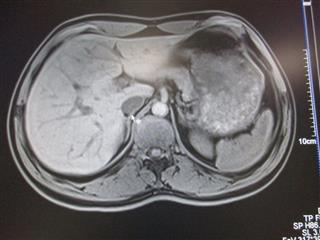

IRM - Imagerie à Résonance Magnétique

image 1 - Estomac à gauche et Foie Rate Pancréas à droite - Oesophage au milieu.

image 2 - Coupe de la Cuisse - Fémur en noir au milieu, Muscle en blanc et graisse en noir avant la délimitation de la peau

image 1                                                        image 2

Spéciale Dédicace à Marie-Claude, notre Docteur qui nous a accompagnée et a fait ces 3 clichés.